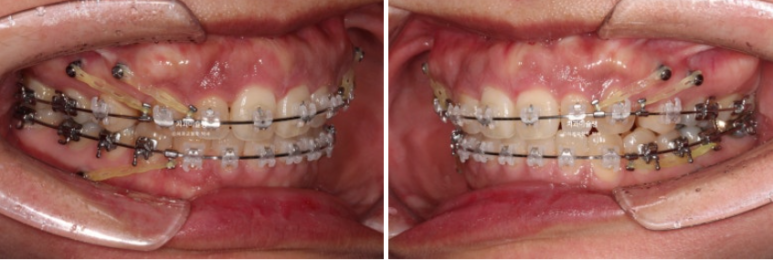

23.10

This is what the patient looked like 10 months after starting treatment.

If you are curious about the treatment method that uses Clippy-C to intrude the upper dentition to correct a gummy smile and protrusion, please refer to the case that Director Baek Eui-seon published as the first author in an SCI journal 10 years ago.

You can see that the gummy smile is gradually improving.

Up to this point, the patient had been coming in regularly every month, so the extraction spaces had narrowed to less than half within 10 months.